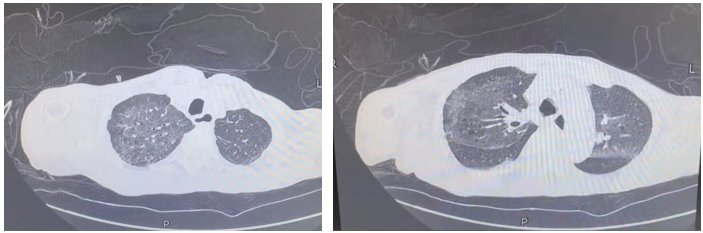

北京中医医院急诊为吴爷爷完善胸部CT后确认:双肺大面积渗出、实变,即俗称的“白肺”,同时双侧胸腔积液明显。老人神志尚清,但精神萎靡,呼吸急促,血氧下降,病情危重。

经过近两周的综合救治,吴爷爷的变化令人欣喜。复查胸部CT显示:双肺弥漫性渗出、实变已明显吸收,“白肺”基本消退。临床症状上,他不再喘憋,咳血消失,血氧恢复正常。